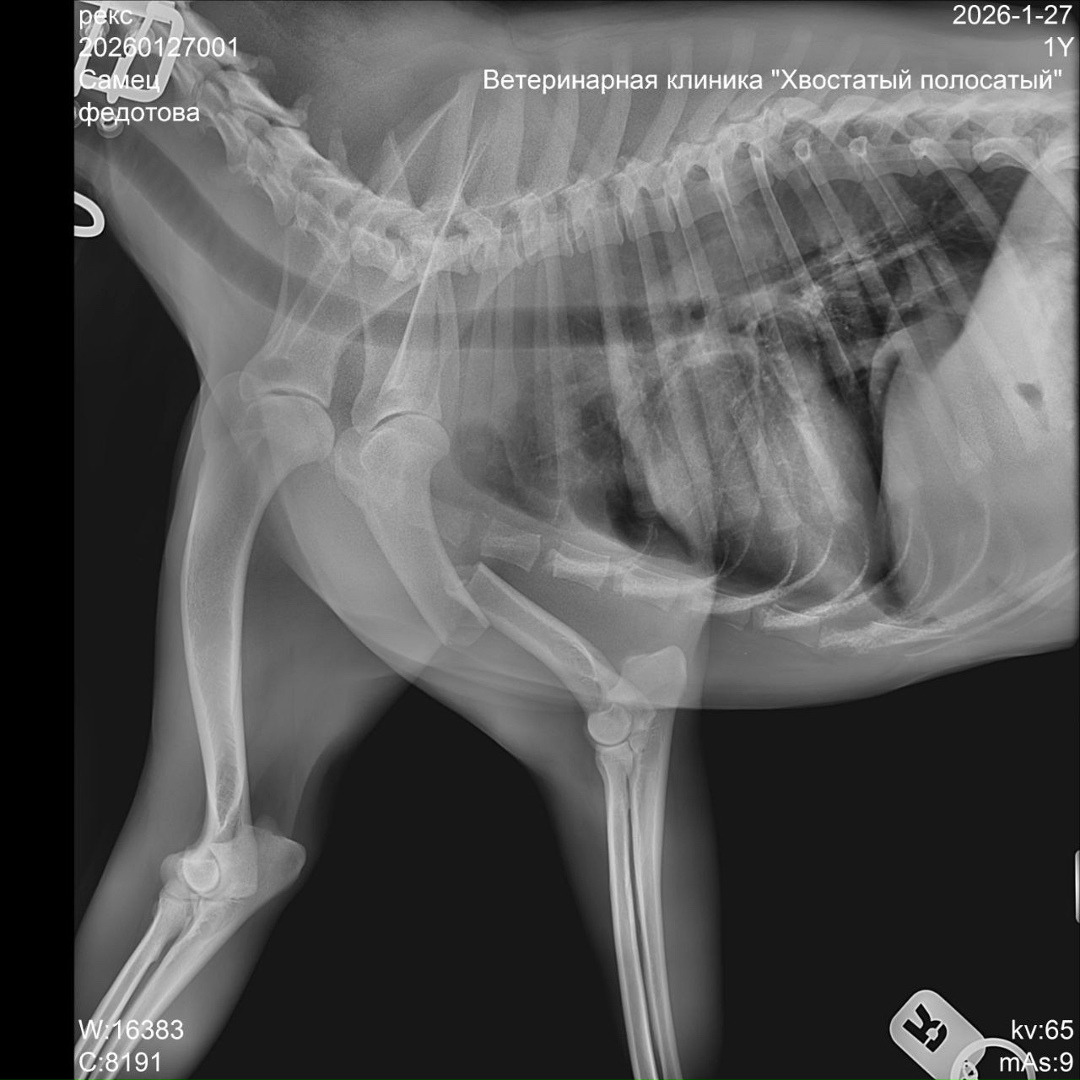

Срочный ‼️ пост сбор!!!!!!! Умоляем помогите!!!!!!Друзья,у нас экстренный сбор!Все кто следит за моей страницей,думаю помнят летом с Абхазии я привезла кошку с опухолью ,котенка и двух щенков,спасибо приюту «Умка»они приняли тогда у меня щенят,вылечили и пристроили в семьи,но сегодня случилась беда Тима(теперь он Рекс)сбила машина у дома,хозяева нашли его утром ,взяли такси и приехали в Пермь с Кукуштана,у Рекса перелом лапы и позвоночника,и черепно мозговая травма,сегодня его оставили на стационаре капать и обезболивать.Нужна операция,которая многодетной семье не по карману.Нас согласились прооперировать в клиникеДойчевет сумма 80000 тыс,я не знаю соберем ли мы такие деньги,но не оставлять же его инвалидом.Сбор буду вести на свою карту,отчитаюсь под постом!Карта Сбербанка 2202206854425829 привязана к моему номеру телефона 89922395800 Лукиных Елена Валентиновна. Пометка Рексу.Спасибо всем кто нас не бросает,прошу помощи в репостах.